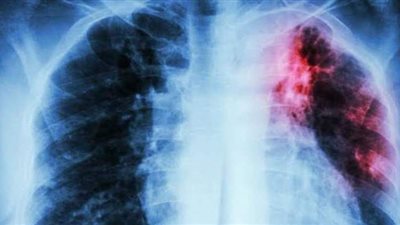

في اليوم العالمي لـ السل، 7 أعراض للإصابة بالمرض الصدري

أكدت منظمة الصحة العالمية أن سوء التغذية والتدخين والسكري تمثل عوامل خطر كبيرة للإصابة بعدوى السل التي قد تتحول إلى مرض اليوم العالمي للتوعية بمرض السل وأشارت منظمة الصحة العالمية في اليوم العالمي للتوعية بمرض السل في 24 مارس إلى أنه يؤثر السل عادةً على الرئتين، لكنه قد يؤثر أيضًا على الكلى والدماغ